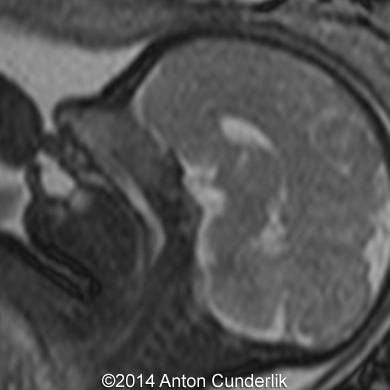

Image 2, 3, 4, 5, 6, 7: 30 weeks of gestation; the images show cystic structure within the fetal tongue that later turned out to be thyroglossal cyst.

Image 8, 9, 10: 33 weeks of gestation; MRI images showing the cystic structure within the fetal tongue representing thyroglossal cyst.